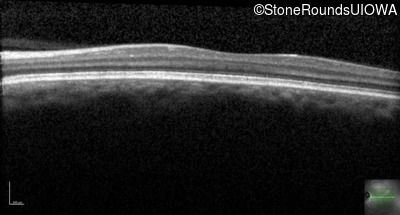

Optical Coherence Tomography - Left - 20/160 -1

Exemplar / OCT Stack